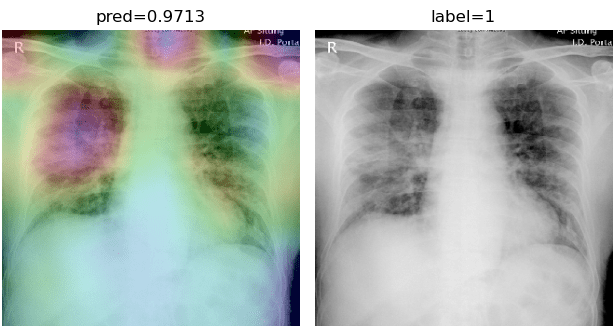

To overcome the aforementioned issues and force the model’s attention to the correct regions of interest (ROIs), we introduce the COVID-CXNet. Our model is initialized with the pretrained weights from CheXNet. A dataset of 3,628 images, 3,200 normal CXRs and 428 COVID-19 CXRs, are divided into 80% as training-set and 20% as test-set. Batch size is set to 16, rather than 32 in previous models, regarding memory constraints. Grad-CAMs of the COVID-CXNet for random images are plotted in Fig. 15.

Refer to caption

Figure 15: Grad-CAM visualization of the proposed model over sample cases

More Grad-CAMs are available in Appendix A. Heatmaps are more accurate than previous models, while an accuracy of 99.04% and an f-score of 0.96 are achieved. Table 3 is the confusion matrix of the proposed model.